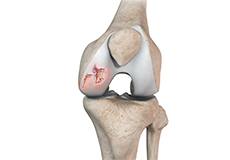

Loose Bodies in the Knee

Loose bodies are fragments of detached cartilage or bone inside the knee joint. These fragments may be free floating (unstable) or may be trapped (stable) within the joint. Depending on the severity, you may have one or more loose bodies in your knee joint.